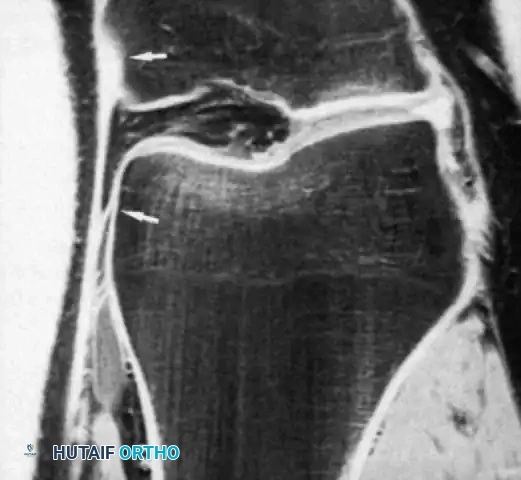

DIAGNOSTIC EVALUATION

The timing of swelling is a critical diagnostic clue. Rapid intra-articular swelling (within 1 to 2 hours) strongly suggests a hemarthrosis, indicative of an ACL tear, osteochondral fracture, or peripheral meniscal tear. Conversely, swelling that develops gradually overnight usually indicates an acute traumatic synovitis.

Physical Examination

The examination must be precise, systematic, and performed as soon as possible before severe swelling and involuntary muscle guarding obscure the findings. Both lower extremities must be fully exposed for comparison.

Image

Observe for ecchymosis, abrasions, and the resting attitude of the limb. Muscle atrophy, particularly of the vastus medialis obliquus (VMO), occurs rapidly following knee trauma and should be noted.

Palpation of the collateral ligaments from their femoral origins to their tibial/fibular insertions is necessary to localize the exact site of pathology. A palpable defect is occasionally present immediately after injury, particularly at the tibial insertion of the MCL or the fibular insertion of the LCL.

Stress testing is the cornerstone of the physical examination. Valgus and varus stress tests should be performed at both 0 degrees (testing the capsule and cruciates) and 30 degrees of flexion (isolating the collateral ligaments). The Lachman test, anterior drawer, and pivot-shift tests evaluate the ACL, while the posterior drawer and dial tests evaluate the PCL and posterolateral corner.